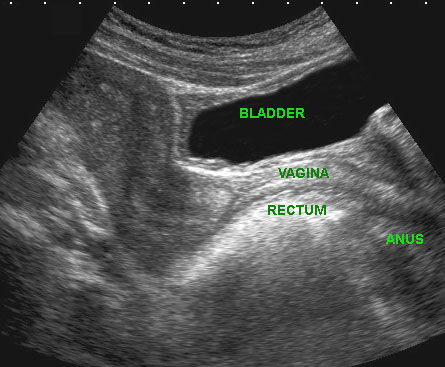

Bệnh lý của niệu đạo, âm đạo đoạn xa và cơ thắt hậu môn có thể được khảo sát bằng đầu dò âm đạo đặt ở vị trí âm hộ (mặt phẳng đứng dọc).

Hình ảnh

Giải phẫu siêu âm bình thường với đầu dò ở vị trí âm hộ